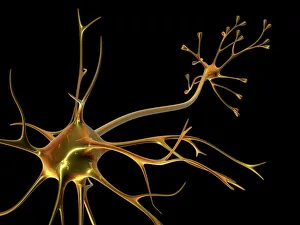

The central nervous system, the intricate network that governs our every thought and movement, is a marvel of complexity. From the delicate cerebellum tissue to the detailed light micrograph capturing its essence, we are reminded of its importance in maintaining balance and coordination. Anatomy comes alive as we explore the human brain from an inferior view. The intricacy of brain fibers is revealed through DTI MRI scans like C017/7099 and C017/7035, showcasing their vital role in transmitting information throughout this extraordinary organ. Artistic renderings bring us closer to understanding the medulla oblongata's significance within the brain. Its portrayal in various artworks allows us to appreciate how it controls essential functions such as breathing and heart rate. As we delve deeper into studying the central nervous system, models of the human brain provide invaluable insights into its structure and organization. Lateral views reveal countless regions responsible for cognition, emotion regulation, sensory perception, and motor control. Microscope slides offer glimpses into nerve cells' intricate architecture—a testament to their ability to transmit electrical signals at lightning speed. Meanwhile, glial stem cell cultures captured under a light microscope remind us of their crucial role in supporting neuronal function. Finally, artistic representations unveil the limbic system's enigmatic nature—an interconnected web responsible for emotions and memory formation. These captivating artworks allow us to visualize this complex network within our brains. Exploring these hints provides a glimpse into the awe-inspiring world of our central nervous system—the very foundation upon which our thoughts, actions, memories reside—reminding us just how remarkable our brains truly are.